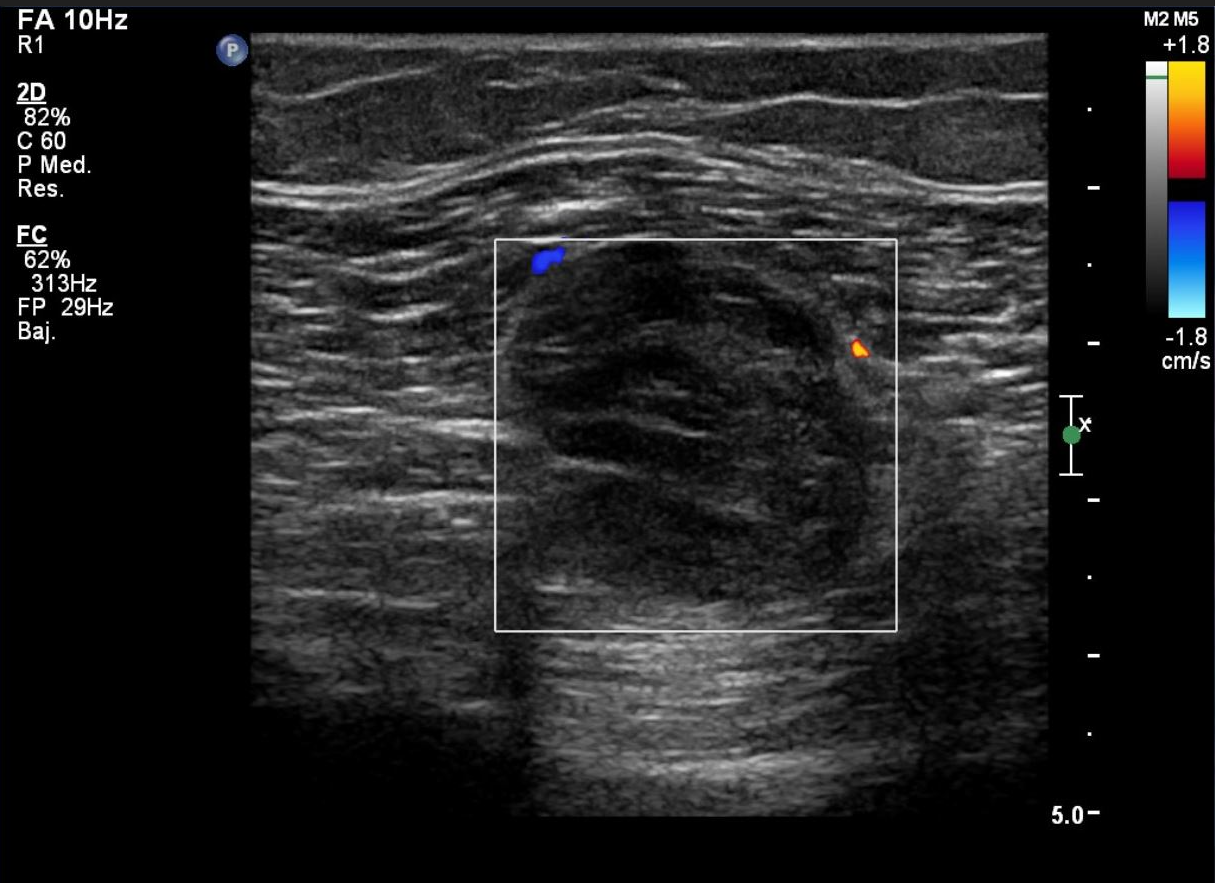

Ecografía Doppler.